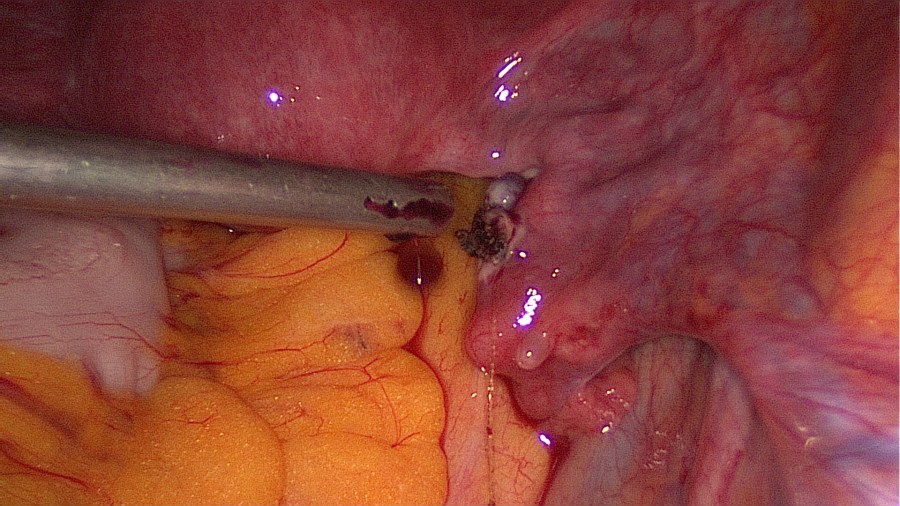

Linear salpingotomy: open the tube directly over the tubal pregnancy with a straight incision made with a monopolar needle (Taran, F-A et al., 2015).

Grasp the contents with an atraumatic grasper and expell the tubal pregnancy en bloc. Failure to do so may increase risk of persistent ectopic tissue. Alternatively this may be performed with suction or aquadissection.